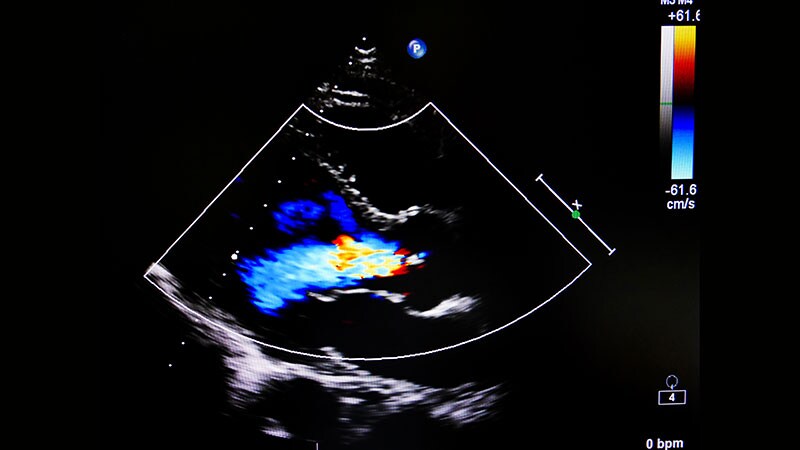

HFSA 2022Optimized HF Meds May Lessen MR Severity, Avoid Invasive TherapyPatients with heart failure and mitral regurgitation should get at least 6 months of optimized guideline-directed medical therapy before invasive mitral repair is considered, researchers say.